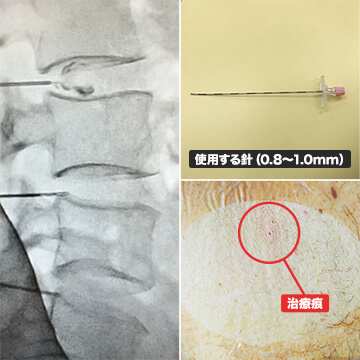

治療内容

損傷した椎間板に特殊な薬剤を入れ、椎間板機能の改善を目的とした治療方法です。特に変形したり、狭くなっている椎間板に対して治療を行っています。

- 3~12ヵ月で症状の改善が期待できます。

- 副作用

- 治療後2週間程度は一時的に症状が悪化する可能性があります。また椎間板の容量が増えたことにより周りの筋肉や靭帯が広がることによって筋肉痛や腰の違和感が出現することがあります。